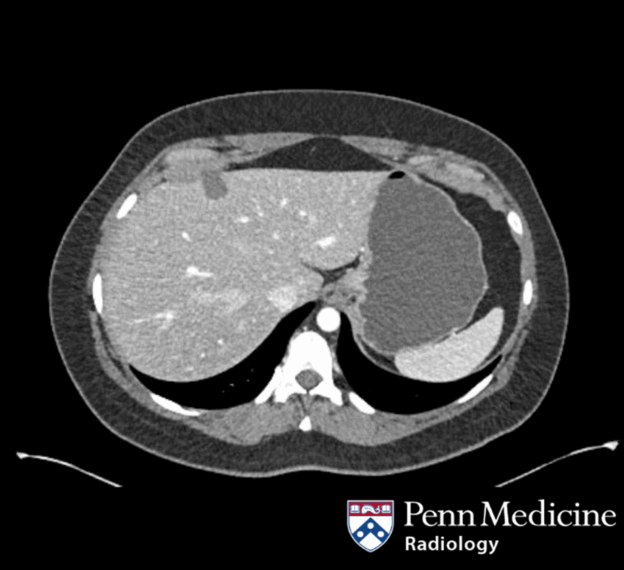

37-year-old man with abdominal pain and incidental hepatic lesion

A 37-year-old man presented with abdominal pain and an incidental hepatic lesion.